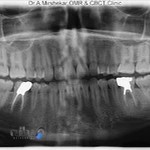

امروزه با پیشرفت علم از روش های زیادی برای تشخیص بیماری ها استفاده می شود که یکی از مهم ترین های آن رادیولوژی می باشد. عکس برداری از نقاط مختلف بدن با استفاده از امواج رادیویی در همه تخصص های پزشکی از دندان تا استخوان و حتی جمجه نیز رواج دارد و به همین علت است که برای تشخیص دقیق تر و انتخاب روش درمانی مناسب تر همه ما به یک مرکز رادیولوژی در نکا نیاز داریم. بدون شک همین حالا می توانید در نزدیکی خود بهترین مراکز رادیولوژی در نکا را پیدا کنید و از آن بهره مند شوید. اما اگر تا کنون نتوانسته اید یک مرکز مناسب جهت انجام رادیولوژی در نکا پیدا کنید کافیست با ما در این مطلب همراه باشید و در کمترین زمان ممکن بهترین مرکز رادیولوژی در نکا را پیدا کرده و از آن بهره مند شوید.